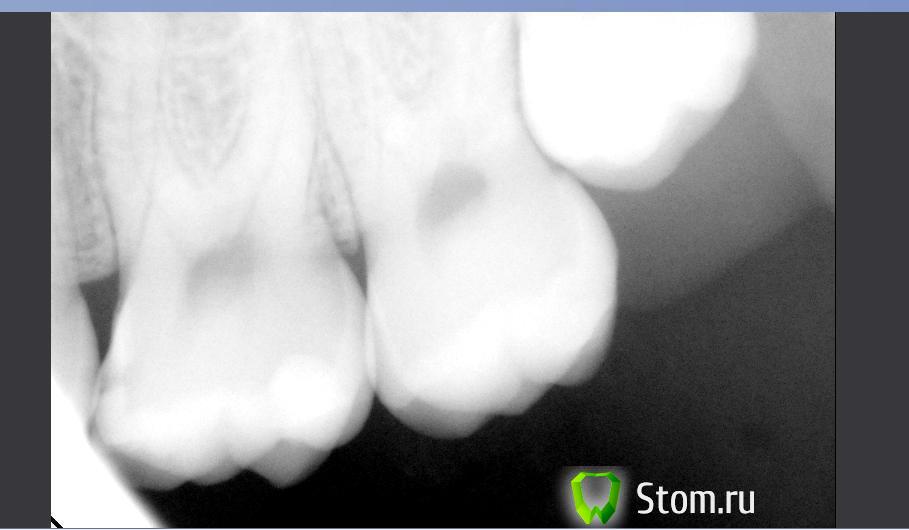

Ferny Опубликовано 9 декабря, 2011 Поделиться Опубликовано 9 декабря, 2011 Ув. коллеги, помлгите пожалуйста! Вот такой случай: Пац. жалуется на тупую ноющую боль в нижней правой шестёрке, которая возникает во время жевания какого либо твёрдого куска пищи, боль сама проходит в течение 20 минут. Пац. говорит что помогает паста Sensodyne и боль проходит. На 46 зубе стоит большая пломба с жевательной поверхности а так же с букальной на шейке зуба тоже небольшая пломба имеется, немного дефектная. Есть небольшая атриция бугорка. На верхней челюсти стоит мостПеркуссия немного болезненная, когда нажимаю на зуб 46 , то она чувствует болезненность, так же зуб 45 тоже реагирует на перкуссию. Пальпация в области верхушки корня безболезненна. Она раньше обращалась с этой проблемой к другим стоматологам, но ей не делали рентген и говорили что всё нормально и немного стачивали пломбу. В обычном положении когда зубы вместе её ничего не беспокоит. 1) Вот рентген, скажите ваши мнения по поводу зуба 46 и 45. 2) и ещё второй снимок зуба с кариесом на зубе 26 (другой пац). Опыта у меня мало, так что не знаю точно, звала старших коллег чтоб посмотреть, так они не нашли вобще ничего и сказали дырки нет, я сделала рентген и увидила что есть.Кариес уже в дентине? тоисть надо срочно делать? Спасибо заранее =) Ссылка на комментарий

anvladd Опубликовано 10 января, 2012 Поделиться Опубликовано 10 января, 2012 На 26 кариес на медиальной поверхности Ссылка на комментарий